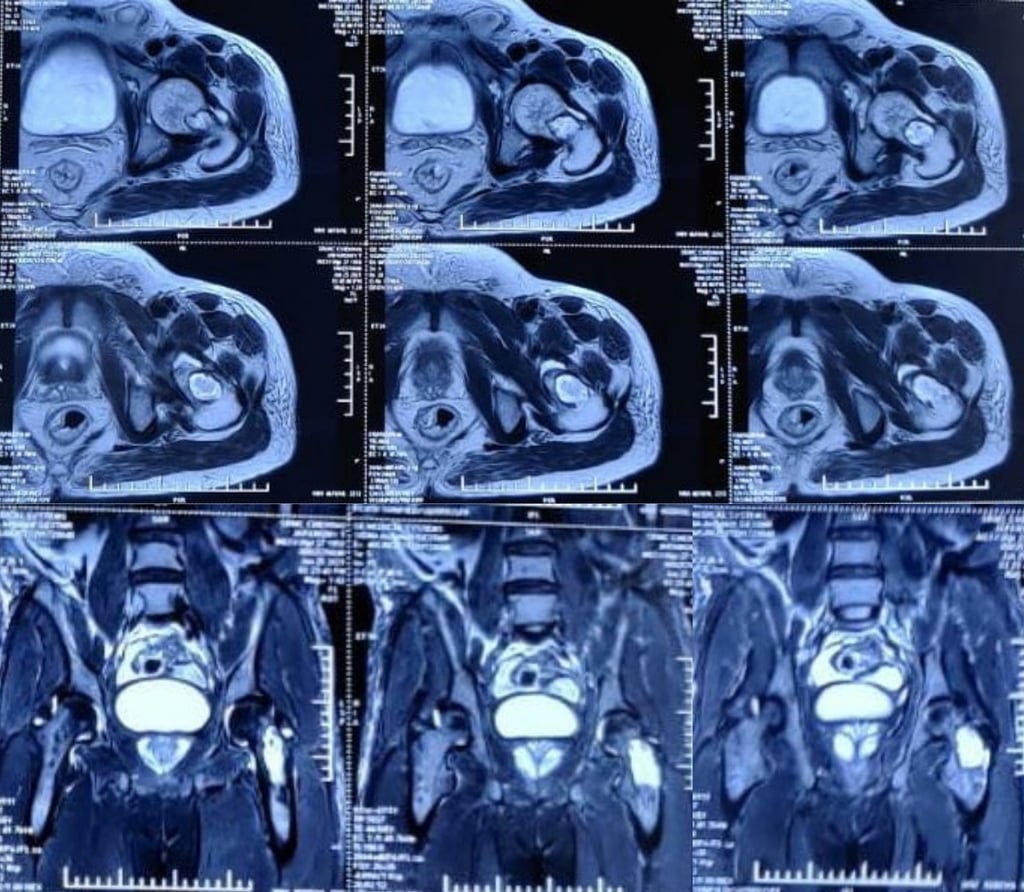

Inverted horn myositis ossificans circumscripta in the pelvis and bilateral adductors

Myositis ossificans is a benign ossifying lesion which can affect any soft tissue including subcutaneous fat, tendons, muscles and nerves. The common locations include the elbow, hip and knee. The pelvis is an extremely rare site for myositis ossificans which has only been described anecdotally in the past. Myositis ossificans involving the adductor muscles- adductor longus or adductor magnus is also an uncommon location, with only a few case reports of its occurrence in athletes. Myositis ossificans involving the adductor longus has been reported to occur in the form of a long, slender, pencil shaped ossification, however the inverted horn is being reported for the first time.